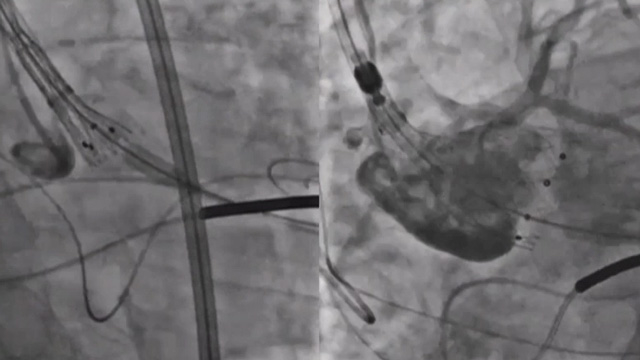

Complex PCI in a TAVI patient - LIVE case

20 May 2025 – From EuroPCR 2025

An 84-year-old patient with a history of ischemic stroke in 2017, hypertension, diabetes, dyslipidemia, and a preserved LV function (63 %) presented with a severe symptomatic aortic stenosis. The coronary angiography revealed a severe and calcified stenosis of the distal left main.

Operators implanted an Edwards Sapien...